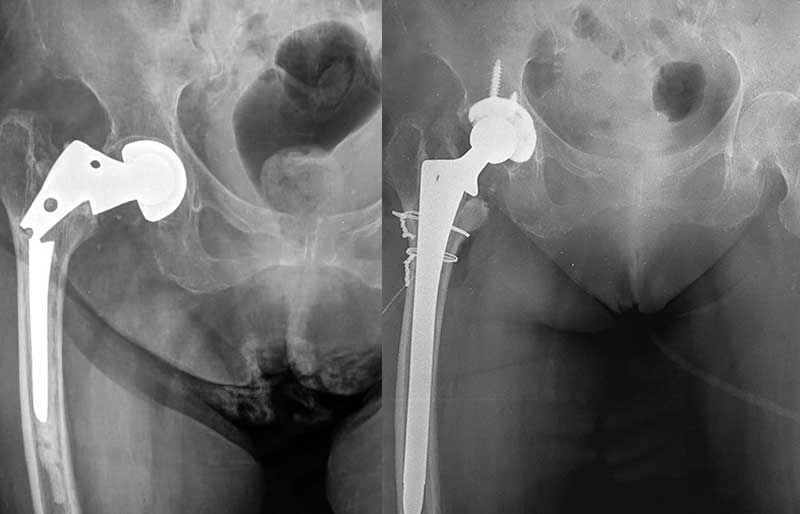

Operasi penggantian sendi panggul adalah suatu operasi untuk mengganti sendi panggul yang rusak dengan sendi buatan yang disebut prosthesis. Penyebab utama kerusakan sendi panggul adalah osteoartritis (baca penjelasan tentang “Osteoartritis”) dan sendi panggul adalah sendi terbanyak kedua setelah lutut yang terserang penyakit ini.

Operasi penggantian sendi panggul merupakan pengobatan terbaik untuk osteoartritis panggul stadium yang berat. Ada empat tujuan operasi ini, yaitu menghilangkan rasa sakit sendi yang telah rusak, memperbaiki lingkup gerak sendi yang sebelumnya kaku dan terbatas, mengembalikan kemampuan penderita melakukan aktivitas harian tanpa rasa sakit, dan meningkatkan kualitas hidup sehingga penderita kerusakan sendi dapat menjalani hidup secara aktif bebas dari nyeri sendi panggul.